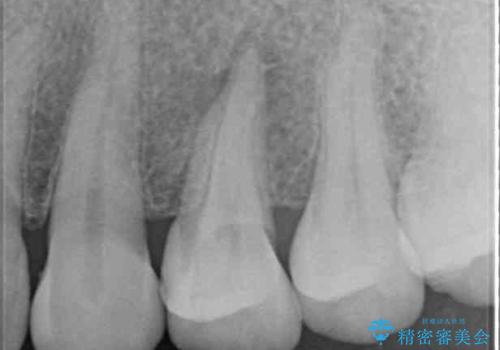

診査の結果、既に歯の神経は失活しており、レントゲンより根尖部に病変を認めました。

補綴後6ヶ月経過しレントゲンを撮影したところ、根尖周辺の病変が消失していることが確認できました。